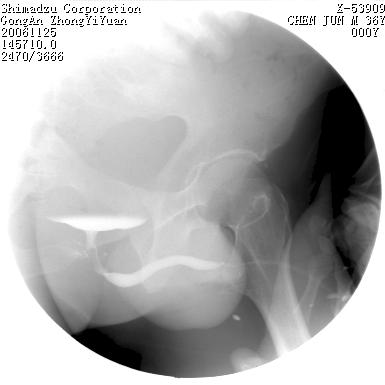

男 66岁 排尿困难半年;此人腹腔及腹膜后积液.

是结石或息肉,为什么在不同的时候形态会有变化?另有一点须说明的是尿道两边的高密度阴影应该是造影剂逆流吧.

1、后尿道的充盈缺损有变化可能与压力有关;

2、两侧后尿道周围的略高密度影亦有可能为造影剂逆流,有条件的话做个ct吧!

后尿路精阜水平充盈缺损,考虑结石或占位病变可能,建议mri检查,精阜水平尿路周围条索状密度增高影,考虑造影剂逆流入输精管或周围静脉。